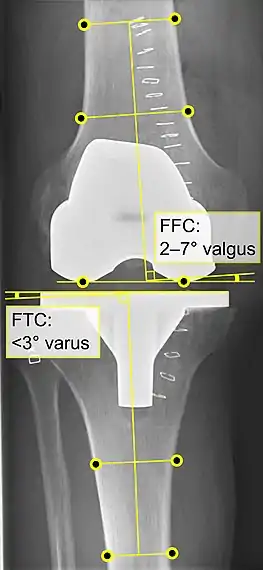

Knee replacement is routinely evaluated by X-ray, including the following measures:

- FFC: frontal femoral component angle. It is typically regarded as optimal when being 2–7° in valgus.[57]

- FFC: frontal femoral component angle. It is typically regarded as optimal when being 2–7° in valgus.[57]

- FTC: frontal tibial component angle, which is regarded as optimal when being at a right angle. A varus position of more than 3° has generally been found to increase the failure rate of the prosthesis.[57] - Anterior femoral notching (the femoral component causing reduced thickness of the distal femur anteriorly), seems to cause an increased risk of fractures when exceeding about 3 mm.[58]

- Anterior femoral notching (the femoral component causing reduced thickness of the distal femur anteriorly), seems to cause an increased risk of fractures when exceeding about 3 mm.[58]

- LTC: lateral (or sagittal) tibial component angle, which is ideally positioned so that the tibia is 0–7° flexed compared to at a right angle with the tibial plate.[57]